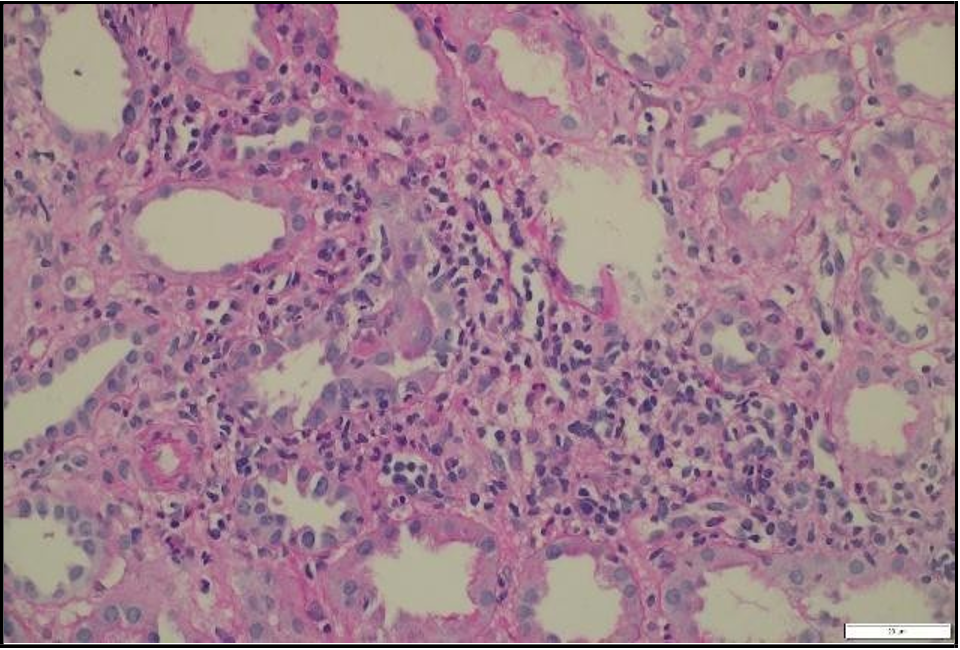

A percutaneous transplant kidney biopsy performed on January 30, 2024, revealed acute cellular rejection, classified as Banff 2019 vascular type, grade 2A, along with mild acute tubular injury [Figure 3].  The  patient  was  treated  with  pulse  corticosteroids  and antithymocyte globulin (thymoglobulin) at a cumulative dose of 3 mg/kg. Her renal function improved significantly, with creatinine decreasing to 56 µmol/L, and she was discharged home on February 4, 2024.

Figure 3: Light microscopy of transplant kidney biopsy showing severe lymphocytic tubulitis (t3), moderate interstitial inflammation (ti2), and mild intimal arteritis (v1), consistent with acute cellular rejection (Banff 201G; vascular type, grade 2A).

A repeat percutaneous kidney biopsy was performed and histopathologic analysis revealed 18 of 34 glomeruli globally sclerosed, indicating significant chronic glomerular injury. There were features consistent with urinary tract infection, and moderate peritubular capillaritis was noted, although definitive glomerulitis was absent, C4d stain negative.